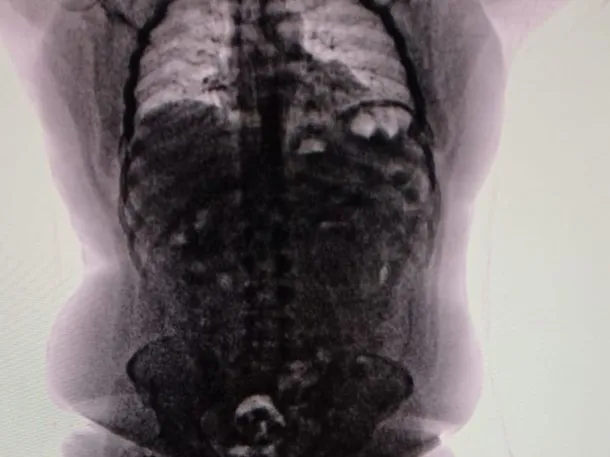

Tras un control con escáner corporal, se confirmó que transportaba múltiples cuerpos extraños en su interior. Fue inmediatamente internado en el Hospital de Ezeiza, donde permaneció bajo estricta vigilancia médica y policial durante cuatro días, período en el cual evacuó las 90 cápsulas que totalizaron 698 gramos de cocaína.